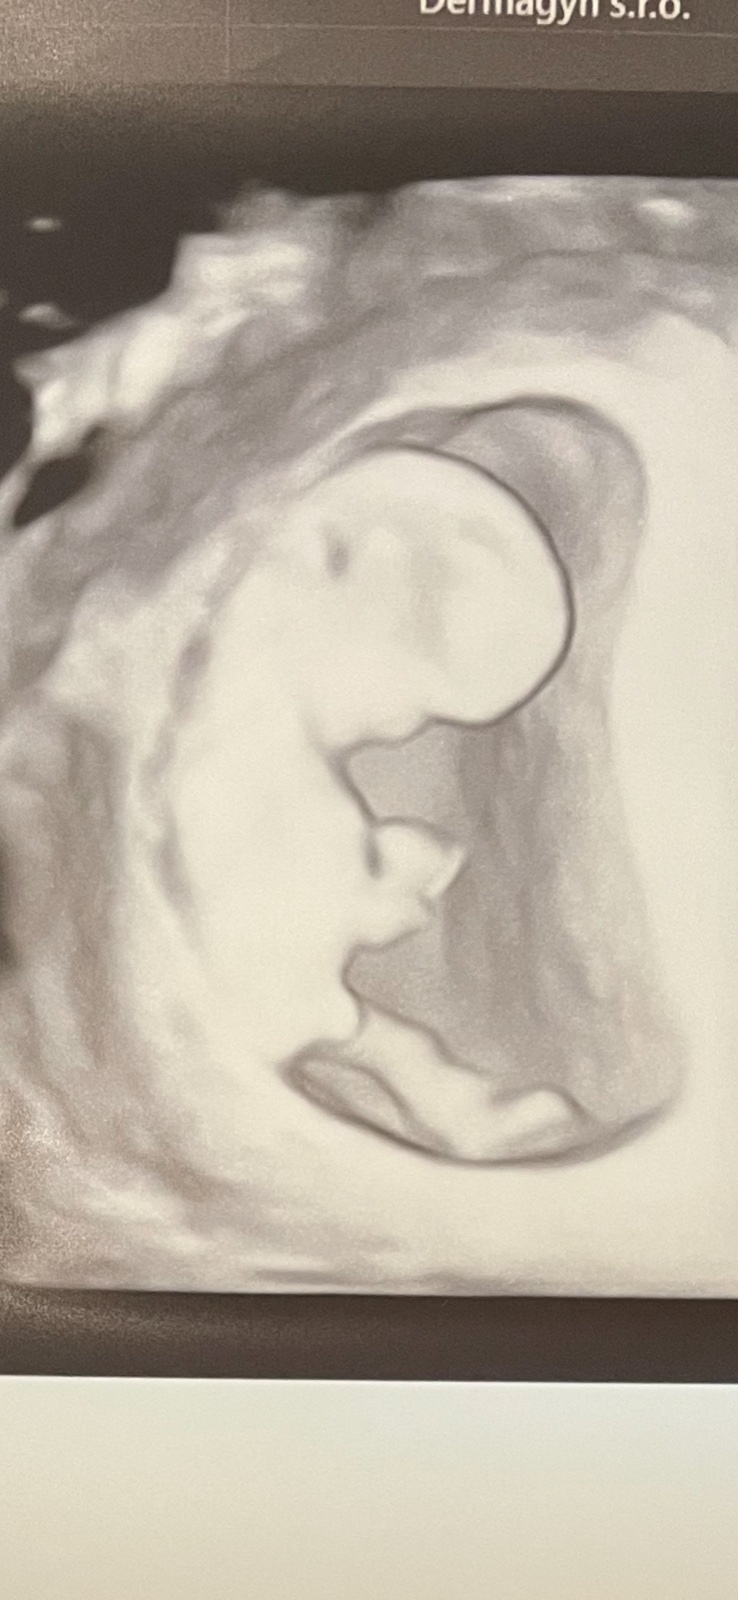

Bude to chlapček alebo dievčatko?

Podkla sklonu a skull teorie skor chlapcek, ale to je v tomto veku na 3D strasne tazko rozoznat...na 2d to vidis ten falicky vybezok omnoho lepsie ten uhol...

@anavixy ano da sa to - vybezok smeruje od chrbtice hore, takze naznak chlapca, celicko je spicate - zas chlapec, hlavicka hranata - zas chlapec... dievcatka mavaju oble cielko a aj hlavicku, falicky vybezok subezne s chrbticou...ale vsetko su to teorie no...